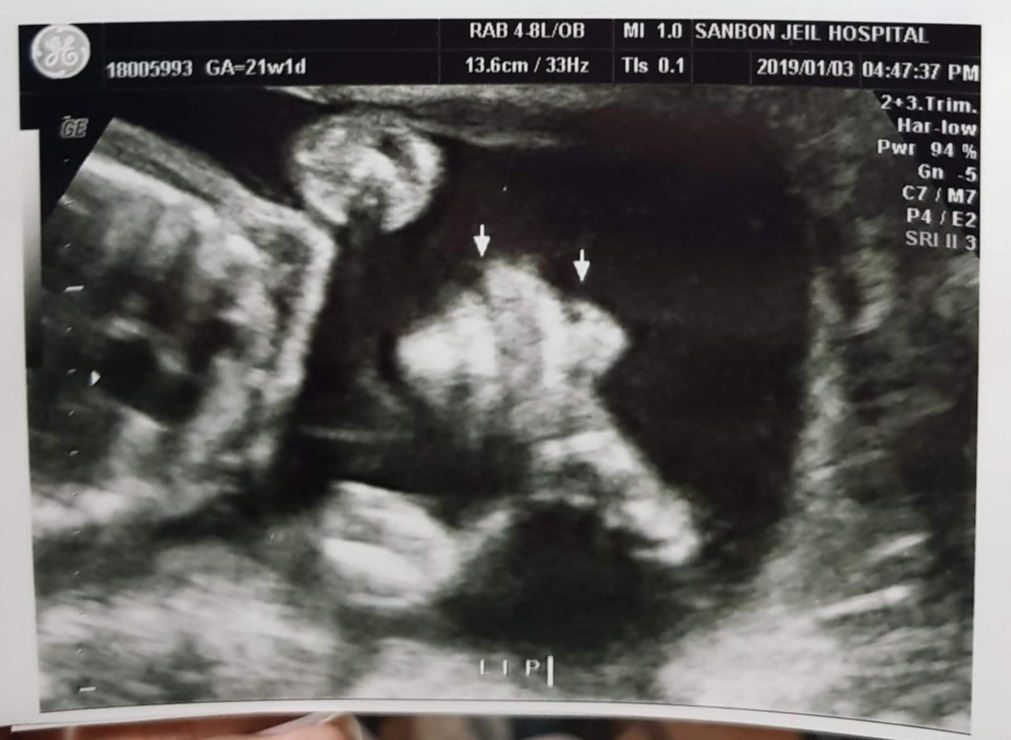

짠짠이 21주 차

21주.

기형아 검사에 마음 졸인 엄마 아빠와는 상관없이 짠짠이는 한껏 자라서 이제 아기집이 좁다. 이사도 하고 새해를 맞이하여 새로운 환경에서 잘 자라는 중. 아내는 이제 누가 보기에도 임산부 티가 난다. 좁아진 엄마 뱃속에서 열심히 뒹구느라 배를 슬슬 차기 시작했다. 이 즈음 아내는 첫 태동을 느끼고 짠짠이가 마음에 더 훅 들어와 버렸다고. 초반에는 태동이 오면 나에게도 느끼게 해 주려고 애를 썼는데 나중에는 시시때때로 짠짠이 발길질을 느끼게 되었다. 낮은 음성의 아빠 목소리가 좋다고 하여 아내 배를 만지면서 종종 태담을 하던 시기. 태담이라고 해봤자 "어~ 음~ 오~ 우~ 아~" 이런 갖가지 의성어를 들려주는 정도였는데, 아내는 어른의 말을 하라고 성화였다. 그래서 가끔 태교동화도 읽어주고. 그런데 나는 왠지 짠짠이와 짠짠이 언어로 대화를 하고 싶었다. 물론 그 의성어들이 짠짠이 언어인지는 확인할 길이 없지만. 어른 말은 엄마가 해줄 테니 나는 짠짠이 말로! 뭐 이런 이상한 고집.